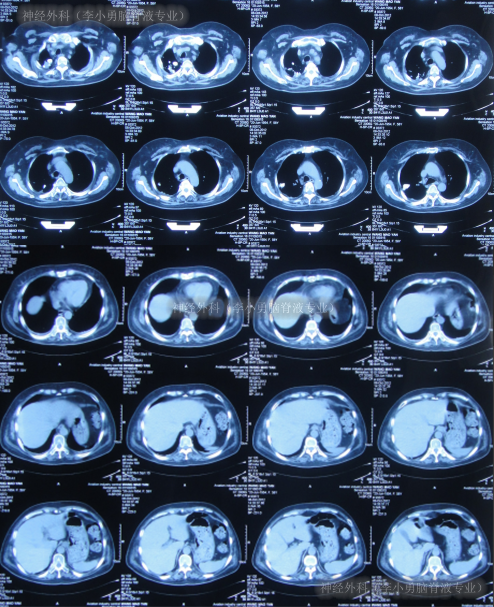

第3家医院给予对症治疗13天后仍无明显好转。于是2012年2月21日转入第4家医院:当地的某胸科医院行抗结核等治疗,在住院期间间断出现发热,最高体温39.4℃,给予物理降温或药物治疗后体温可下降正常,但病情没有好转反而加重:昏迷4次,给予甘露醇脱水治疗后可逐渐清醒,治疗期间查头颅核磁(图-6),脊髓核磁(图-7),肺部影响(图-8)。

图-8:2012年3月21日肺部影像